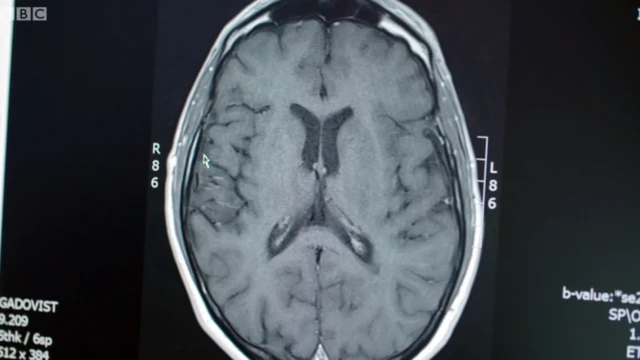

La BBC lo acompañó en una de esas revisiones, en la que los neurólogos compararon un escáner cerebral tomado antes del tratamiento con otro actual.

"Los puntos blancos en el escáner previo al tratamiento son zonas donde hay inflamación activa", explicó el profesor Sharrack.

El neurólogo le mostró a Stephen cómo en las imágenes anteriores al tratamiento había muchos de esos puntos y afectaban a todo su cerebro.

Pero en el actual no había ninguna.